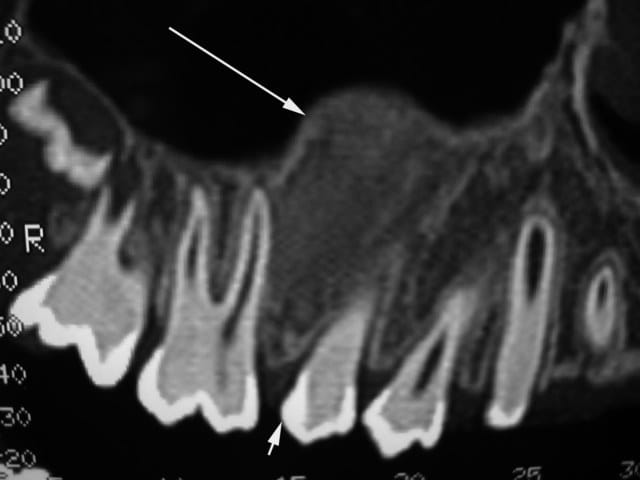

La fille d'un ami, âgée de 12 ans, présente une tuméfaction vestibulaire au niveau du maxillaire. Elle est asymptomatique, évolue conjointement vers le sinus et vers le vestibule.

Une biopsie conclue à l'absence de malignité et penche en faveur d'un fibrome ossifiant ou éventuellement d'une dysplasie fibreuse.

les scan...

second scan...

je prends le post un peu tard, mais presente t elle des signes endocrino : puberté precoce, des taches café au lait au niveau de la peau dissiminées sur le corps ? l'image TDM est tres evocatrice d'une dysplasie fibreuse, vue l'age elle s'inscrit alors comme symptome dans une constellation d'etiologie genetique dite Syndrome de Mc Cune Albright!

avez vous un panoramique ? afin de verifier l'aspect verre de montre depoli?

le fibrome ossifiant ne se traduit pas forcement par cette image radio